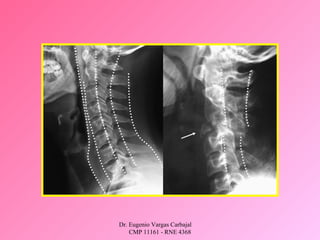

A : MANTENIMIENTO DE LA VIA AEREA – CONTROL DE

LA COLUMNA CERVICAL.